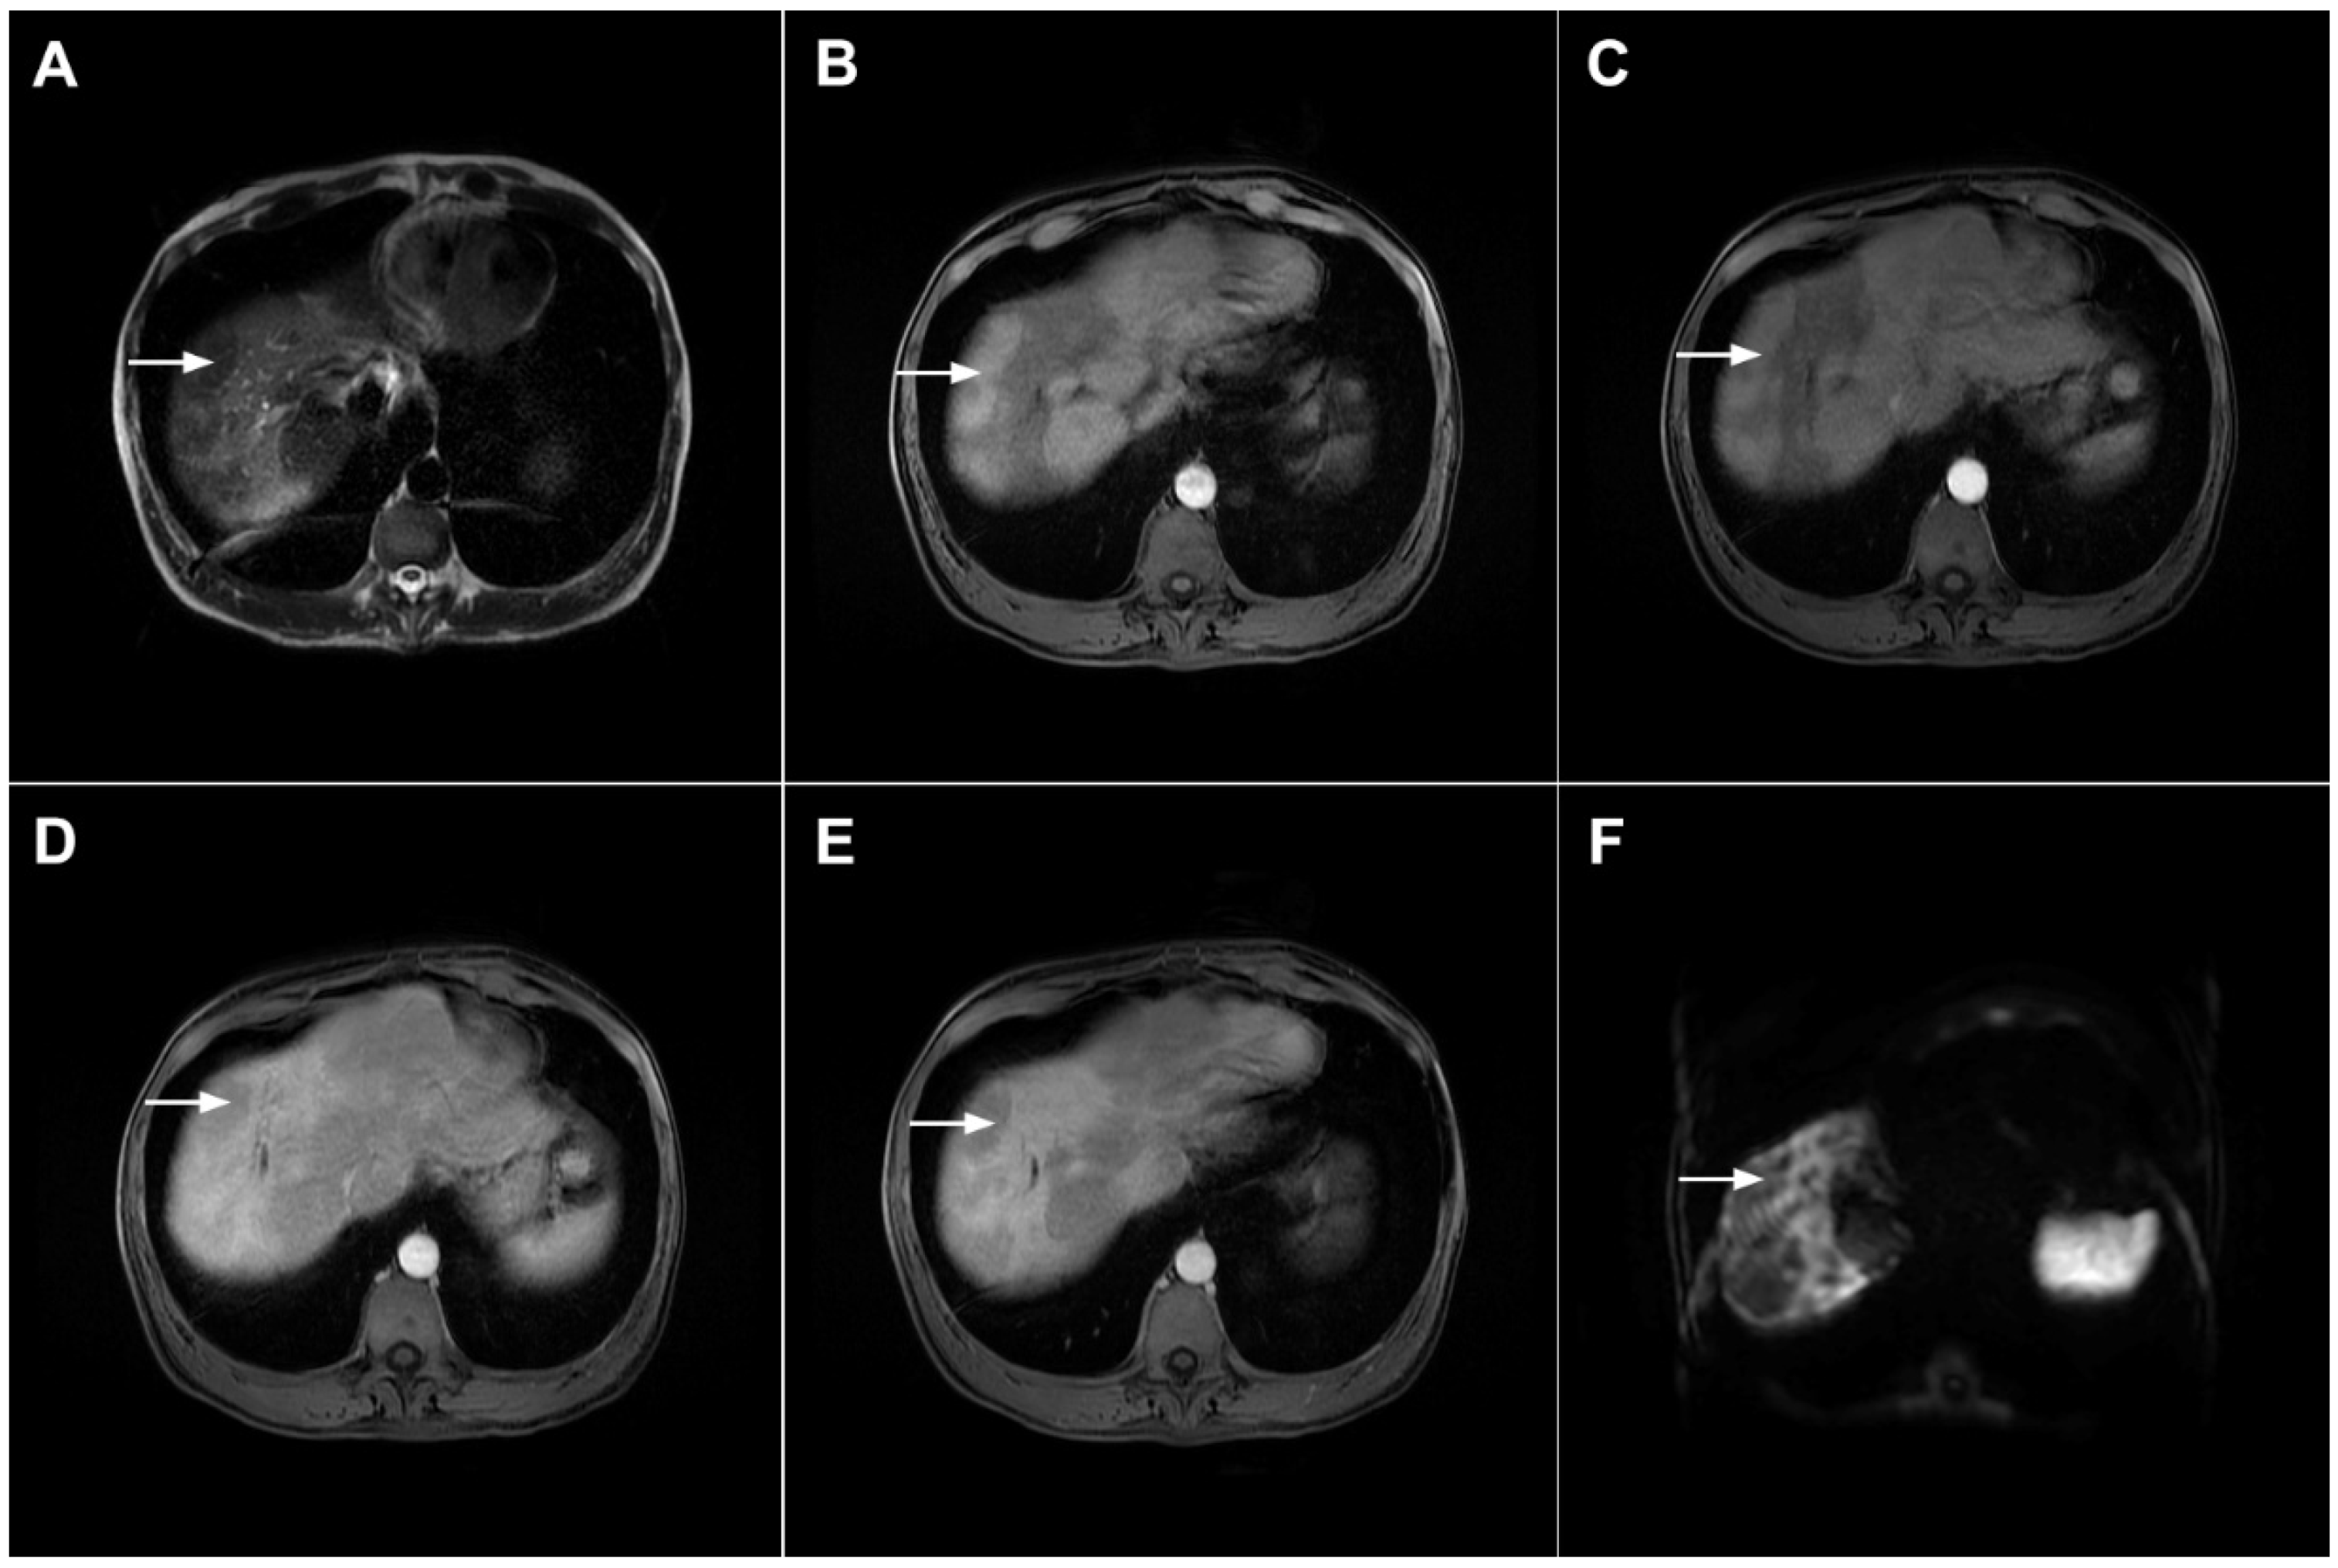

3.1.1. Focal Confluent Fibrosis

3.1.2. Sclerosing Hemangioma

3.1.3. Inflammatory Pseudotumor

3.1.4. Pyogenic Liver Abscess

3.1.5. Liver Echinococcosis